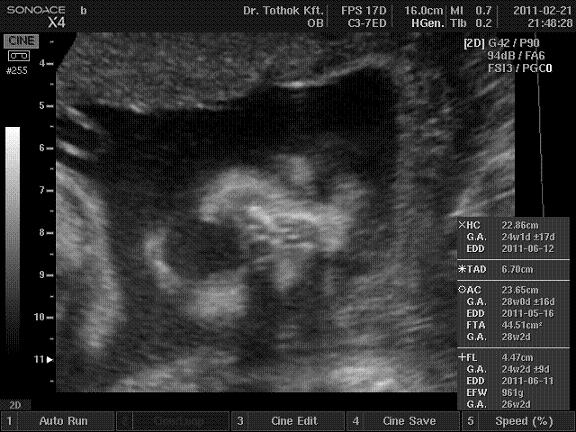

Lilivel császároztak, most úgy futottunk neki a dolognak, hogy ha sikerül, akkor természetes úton hozom világra, de sajnos meg ismételte magát a történelem, elfolyt a magzat víz éjjel (01:20-kor), és nem nagyon voltak fájásaim. 9 óra virrasztás és várakozás után megszületett a döntés, hogy ismét császár lesz. /Oxitocinnal nem indítanak, hogy ne repedjen szét az előző császározás miatti heg a méhen./ Úgyhogy meg kellett várni, amíg dokker visszér a Balcsiról, és utána 12-kor betoltak a műtőben. Megint tanultam, kár, hogy nem lesz 3. mert akkor már még okosabban futottam volna neki a dolognak. Volt fogadott szülésznőm, aki fantasztikusan gondoskodott mindenről. Volt a megbízható dokim, aki profin műtött, vágott, stoppolt, minden király volt. ANESZTEZIOLÓGUST, na azt nem fogadtam... Vazze. Az érzéstelenítést elk....ták, de kőkeményen, felvágtak úgy hogy még mindent éreztem, és nekem kellett szólnom, hogy ez így nem lesz fain. Vagy 5 percig bizonygattam, hogy de én ezt érzem, amíg rájöttek, hogy jééé én ezt érzem.. khmmm.. és akkor gyorsan elaltattak... Aztán úgy ébresztettek fel a folyosón, hogy vagy még nem hatott a fájdalom csillapító, vagy a menet közbeni altatás miatt volt egy flash back, de mindenesetre a frissen szúrt gerincem ellenére szó szerint fetrengtem, üvöltöttem és zokogtam a fájdalomtól, majd ismét filmszakadás, és az örzőben tértem ismét magamhoz, szerencsére akkor már nem voltak ilyen mértékű fájdalmaim.... szóval ha még egyszer neki futnék, akkor az altató orvost is kiválasztanám előre némi kis pénzért. Terveztem ugyan, hogy majd a műtét után adok az anesztesnek is egy kisebb borcsit, de ezek után...egy túróst! ...

:):) De nem számít, ezen túl kell lépni. A baba gyönyörű, az ijesztgetések ellenére egészséges, és mindenki jól van. Ja és a 4 hét alatt hízott 1,1 kilót...